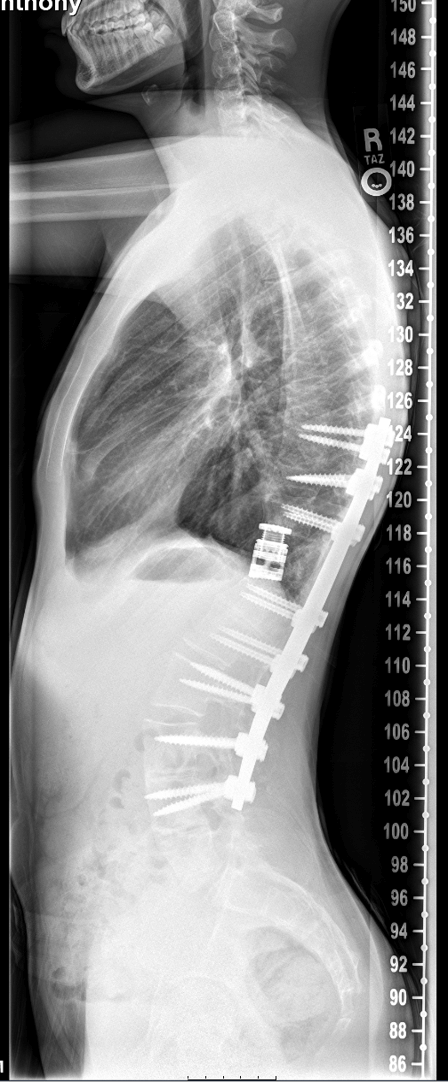

A 15-year-old boy diagnosed with congenital kyphosis and scoliosis as an infant was the first teenager to undergo a complex vertebral column resection surgery in Northeast Ohio. Over 12 hours, Michael Glotzbecker, MD, Division Chief of Pediatric Orthopaedic Surgery at UH Rainbow, partnering with Christopher Furey, MD, Chief of the Spine Center at UH Cleveland Medical Center, rebuilt the teen’s spine. The surgery involved two foot-long titanium rods, 16 screws, removing all of the bone 360 degrees around the spinal cord and an expandable cage to remove the curvature from the patient’s spine and the hump from his upper back. Dr. Glotzbecker is also Associate Professor of Orthopaedics at Case Western Reserve University School of Medicine.

“The goal of the VCR procedure is to remove all of the bone completely from around the spine (in front and behind the spinal cord),” Dr. Glotzbecker says. “This disconnects the spine above and below the curvature and allows us to correct severe, complex deformities. We then need the bone to grow within and around the cage, eventually encasing it in new bone and bridging the gap in the spine where it once curved. Clearly, this was unique and the first pediatric VCR at UH Rainbow and likely the most complex pediatric VCR done in Northeast Ohio.”

As for results, the patient was discharged from UH Rainbow a week after surgery. Just two months after that, he was playing trumpet with his high school marching band. He has returned to all of his activities and is pain-free.